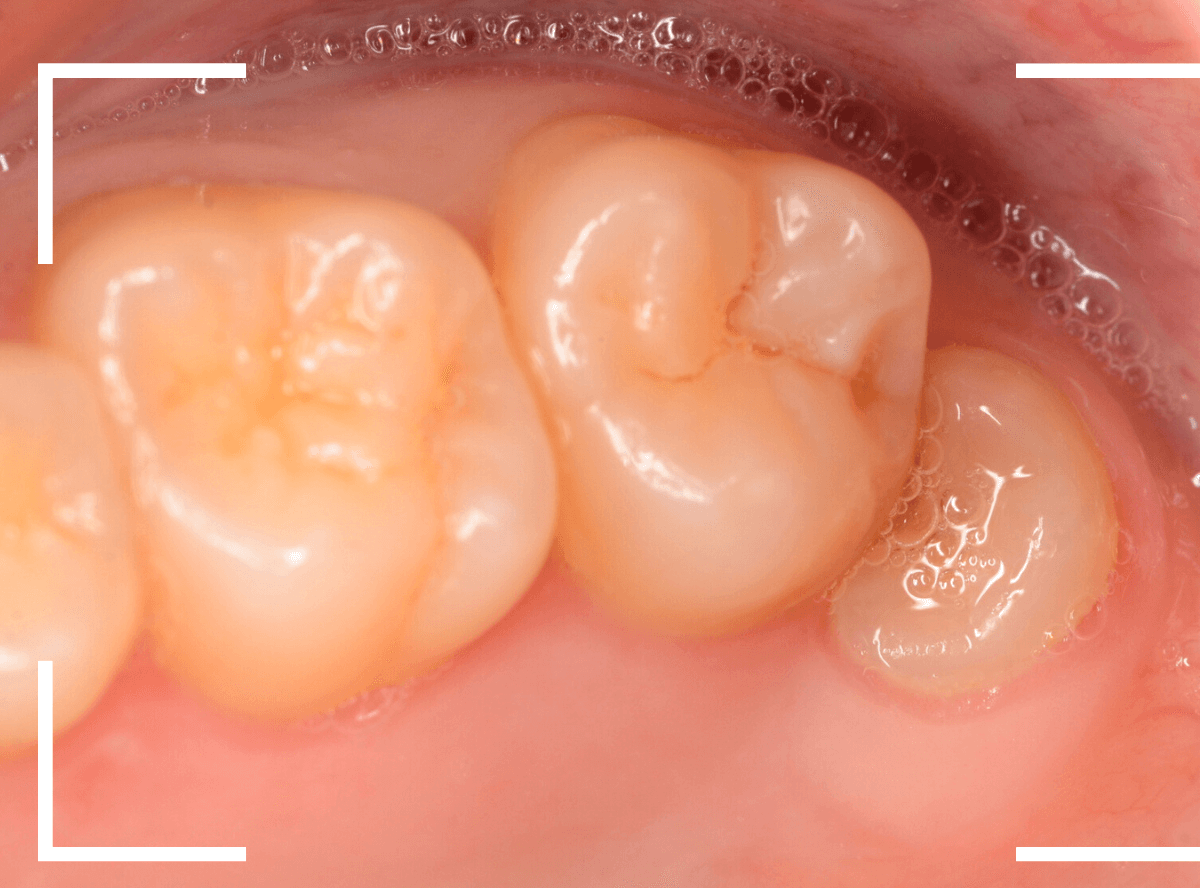

ここでは、比較的簡単なおやしらずの抜歯の例を中心にご紹介します。

このようなおやしらず、あなたはありませんか?